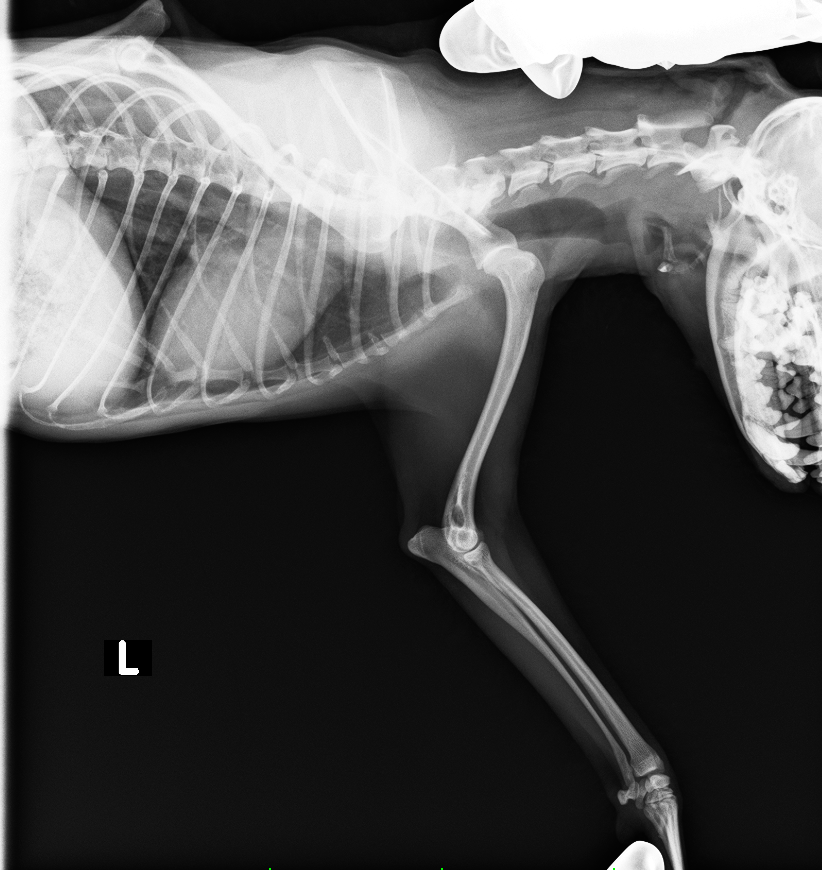

レントゲン検査より、右肩関節脱臼

診断と治療

右肩関節脱臼と診断し、スクリューを上腕骨に挿入し、肩関節を安定化させる

after